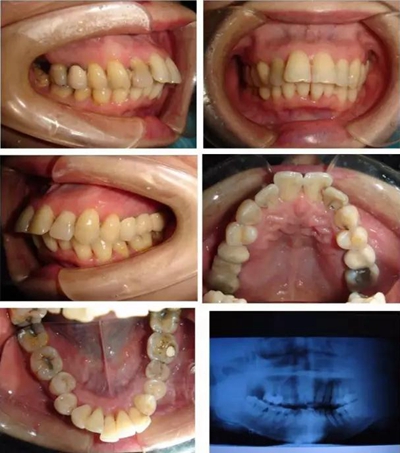

▲ 圖 輕中度患者骨性前突患者

▲ 圖2 典型病例矯治前,患者牙(牙合)像、曲面斷層、頭顱側(cè)位片及側(cè)面像